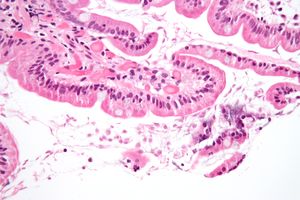

الجياردية المعوية (باللاتينية: Giardia intestinalis) أو الجياردية اللمبلية طفيلي من السوائط يصيب الأمعاء الدقيقة ويتكاثر فيها مسبباً داء الجيارديات (داء اللمبليات).

يتعلق طفيل الجيارديا بطبقة الظهارة في الأمعاء عن طريق قرص بطني لاصق و يتكاثر عن طريق الانقسام الثنائي.

لا ينتشر المرض الذي تسببه عن طريق الدم ولا ينتقل حتي إلي باقي أجزاء القناة الهضمية إذ يظل مقتصرا علي تجويف الأمعاء الدقيقة حيث يقوم طور الـ"تروفوزويت" للجيارديا بامتصاص المغذيات من تجويف الأمعاء وهو طور لاهوائي التنفس.

في حال فحص طفيل الجيارديا تحت الميكروسكوب بعد شقه وصبغه، يكون له شكل مميز جدا يشبه شكل الوجه المبتسم.

وهي وحيدات خلية تتطفل على الجهاز الهضمي العلوي وخاصة العفج و تسبب إسهالات بواسطة ارتباطها بالحجم على الزغابة المعوية للجهاز الهضمي . لها شكلين :

- ناشط : مثل شكل القرد Monkey Face)) له نواتان (يمنى و يسرى ) وله ثمانية سياط يتحرك بواسطتها .

بدراسة البراز الطازج ( خلال 1_2 ساعة ) نرى الجيارديا تتحرك داخل العينة حركتها مميزة متأرجحة (تشبه حركة تساقط أوراق الشجر ). أبعادها 30 ميكرون (وحيدات خلية ) البيوض (40_60) الكيس نصفه (10 ميكرون (غالباً الكيس حوالي النصف وتلك قاعدة عامة ) . الأكياس شكلها بيضوي لها نواتين مميزتين (يمكن أن تنقسما إلى أربعة في الكيس ) وفي المنتصف تتجمع السياط الخارجة داخل الكيس بشكل حرف S .